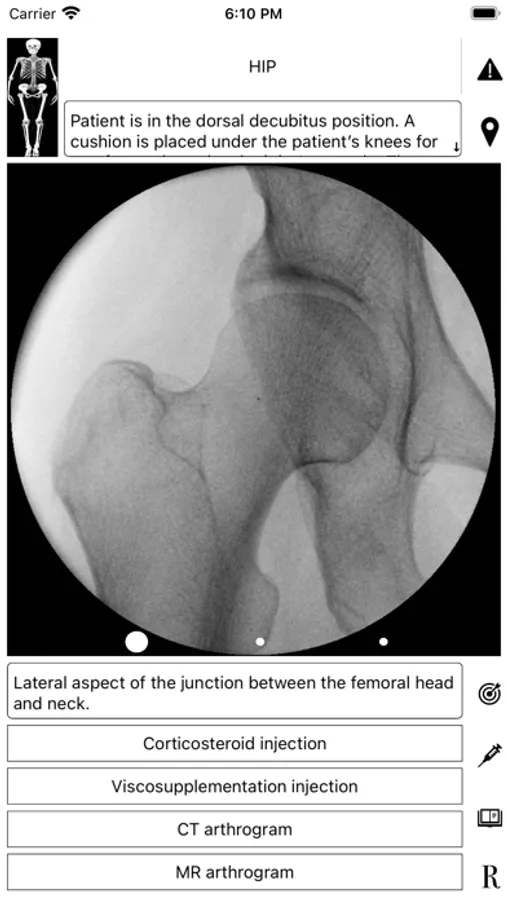

ArthroGuide targets residents, fellows, and physicians who perform fluoroscopically guided arthrograms and pain management injections, including spinal injections. It results from more than 25 years of experience in performing and teaching these procedures.

A visual interface facilitates a quick and efficient review of the information. Find information on patient positioning, puncture site, equipment used, products injected, and the steps to perform therapeutic injections and arthrograms preliminary to an MRI or CT scan. Access relevant references online using hyperlinks directly from within the application. Take advantage of procedural tips, recommendations, and cautionary statements.

ArthroGuide Screenshots